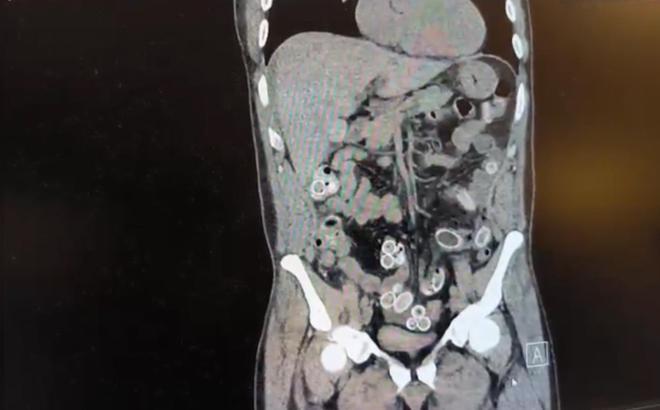

Fas’tan yaklaşık 3 bin kilometre uzaklıktan uçakla Türkiye’ye gelen Cüneyt G., 2 gün sonra karın ağrısı şikayetiyle Fulya’daki özel bir hastaneye başvurdu. Yapılan muayenenin ardından Cüneyt G.’nin tomografisi çekildi. Şüphelinin mide ve bağırsaklarında yabancı madde tespit edilmesi üzerine hastane yetkilileri durumu polis ekiplerine bildirdi.

İhbar üzerine çalışma başlatan Beşiktaş Asayiş Büro Amirliği ekipleri, doktorlarla görüşme gerçekleştirdi. Doktorların değerlendirmesi sonrası ameliyata alınan Cüneyt Ç.’nin bağırsaklarından, toplam ağırlığı 259,7 gram olduğu öğrenilen 49 esrar macunu çıkarıldı. Şüpheliye ait 1 adet cep telefonu da hastane yetkilileri tarafından polis ekiplerine teslim edildi.